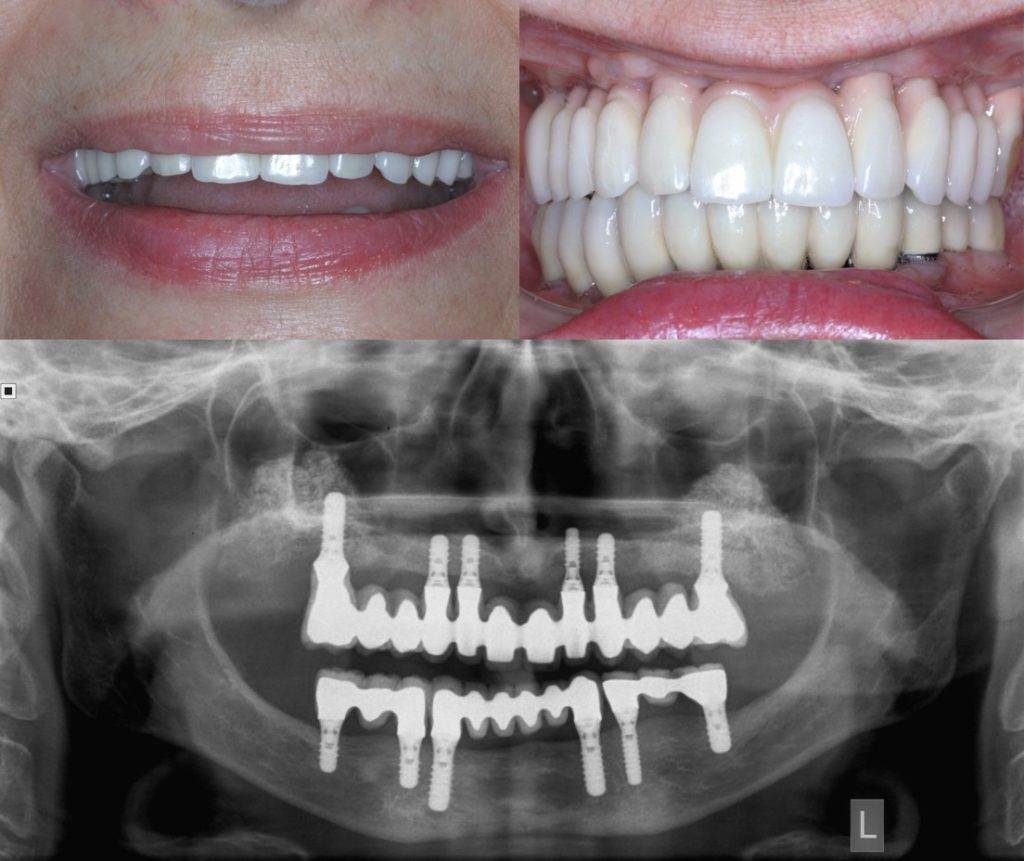

Περίπτωση ολικής αποκατάστασης άνω και κάτω γνάθου με οδοντικά εμφυτεύματα και ακίνητες προσθετικές εργασίες. Η συγκεκριμένη ασθενής απώλεσε τη φυσική της οδοντοφυΐα εξαιτίας προχωρημένης περιοδοντίτιδας (Οδοντίατρος: Ν. Χρονόπουλος).